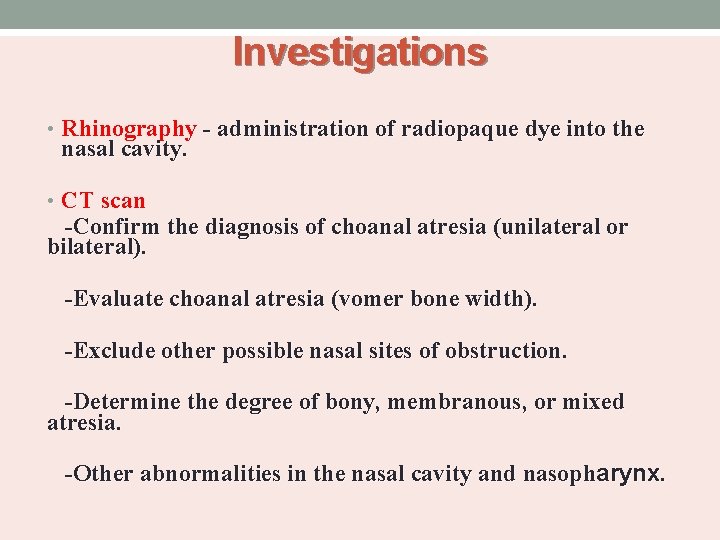

Investigations • Rhinography - administration of radiopaque dye into the nasal cavity. • CT scan -Confirm the diagnosis of choanal atresia (unilateral or bilateral). -Evaluate choanal atresia (vomer bone width). -Exclude other possible nasal sites of obstruction. -Determine the degree of bony, membranous, or mixed atresia. -Other abnormalities in the nasal cavity and nasopharynx.